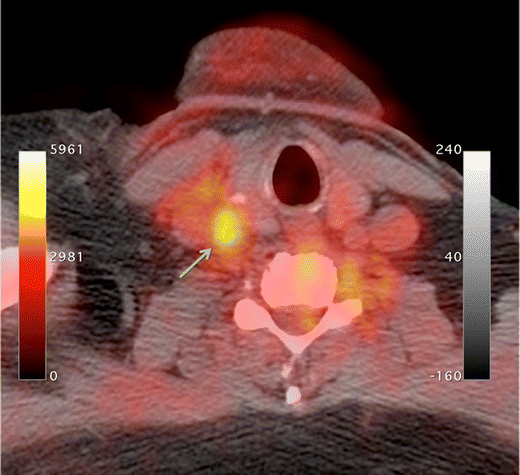

18F-fluorodeoxyglucose (FDG) is the mainstay radioligand in PET imaging and consequently has been the most common radioligand used in imaging studies of atherosclerosis. Originally used for malignancy staging, incidental findings of FDG accumulation in arterial territories during whole-body scans heralded its utility for detecting and quantifying inflammation within atheroma [17]. FDG, a radionucleotide analog of glucose, accumulates intracellularly in proportion to cellular demand for glucose. It is taken up into cells via facilitated glucose transporter member (GLUT) 1 and 3, which are upregulated during atherogenesis due to hypoxia within the atheroma core and once inside the cytoplasm undergoes phosphorylation by hexokinase to become 18F-FDG-6-phosphate. 18F-FDG-6-phosphate lacks a 2′ hydroxyl group and consequently is unable to enter the Krebs cycle and undergo glycolysis, subsequently diffusing slowly out of the cell. This resulting accumulation is readily quantifiable and can be used as a sensitive measure of metabolic activity, particularly given its very high signal-to-noise ratios in tissues without high metabolic activity (such as normal vessel wall and blood). The high concentration of proinflammatory macrophages in the vulnerable plaque provides such a tissue with a high metabolic activity (Fig. 1).

Fig. 1

FDG-PET/CT showing high radiotracer uptake in the right common carotid artery (arrow)